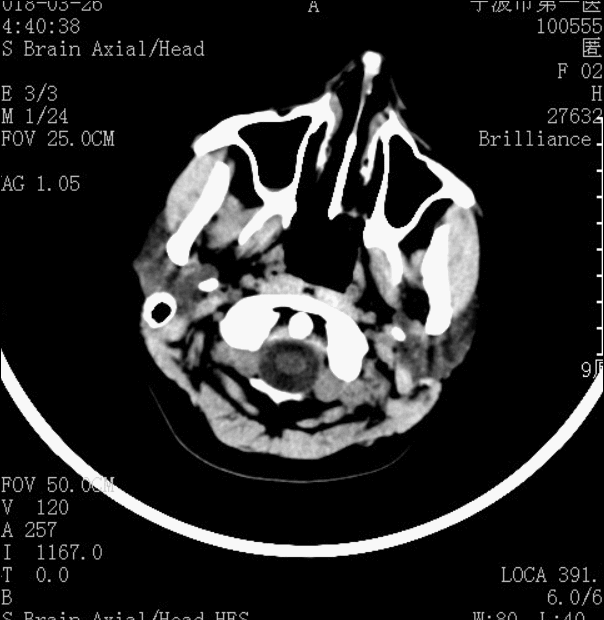

术后造影见AVM已经完全栓塞。

术后CT